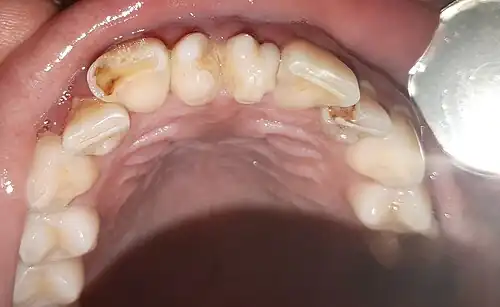

Presentación clínica de un diente supernumerario anterior (Mesiodens).